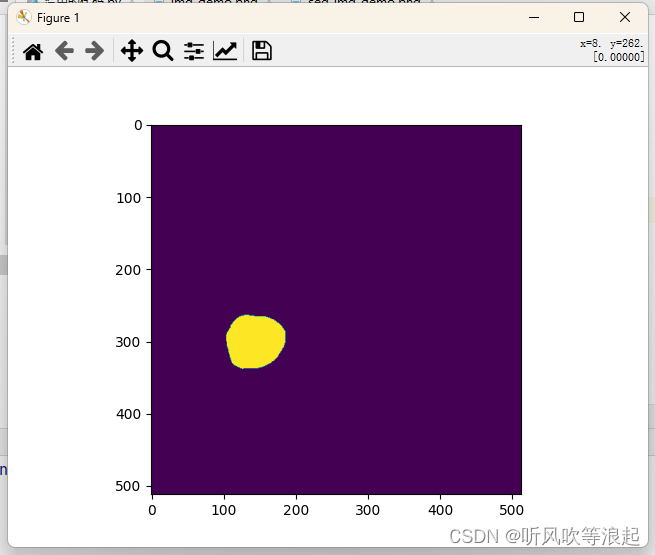

不过这里推理后的图像是黑的,可以根据下面代码显示:

import matplotlib.pyplot as plt

img_path = 'assets/seg_img_demo.png'

img =plt.imread(img_path)

plt.imshow(img)

plt.show()